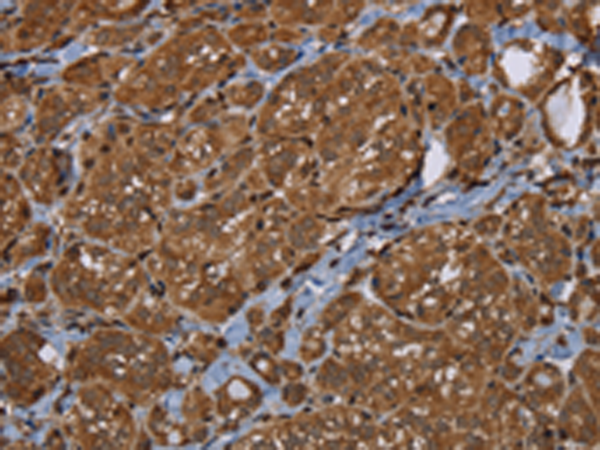

分类: 科研抗体货号: P08401别名: HL应用: WB,IHC反应种属: Human, Mouse, Rat